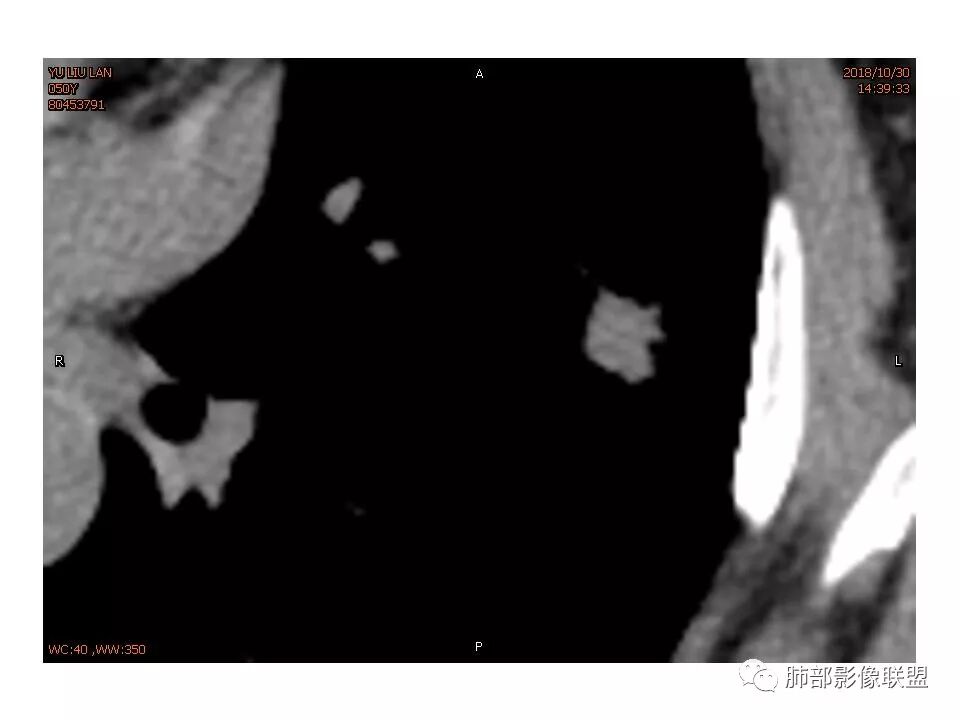

女,50。实性不规则结节,大小12*13mm,分叶、毛刺、胸膜凹陷,牵拉力强,增强渐进性强化,动脉期强化20,静脉期还有进一步强化。边缘强化,点状坏死。

其内血管被破坏。

女性,50岁。U型凹陷、平直征

南边:支持炎性

1.胸膜下略不规则实性密度结节影,孤立,缺乏典型深分叶,可见淡薄边界模糊磨玻璃晕,可见相对细长软毛刺。

2.如南边老师分析,病灶缺乏边缘膨隆优势,甚至部分平直内收。

3.病灶收缩力不强,整体强化程度不显著。

4.综上,病灶更符合炎性,如隐球菌感染等,而不大符合肺腺癌。具体到机化性肺炎略有些出乎预料。